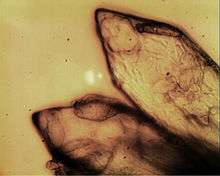

Before techniques of molecular biology were used to localize indolethylamine N-methyltransferase (INMT),[69][71] characterization and localization went on a par: samples of the biological material where INMT is hypothesized to be active are subject to enzyme assay. Those enzyme assays are performed either with a radiolabeled methyl donor like (14C-CH3)SAM to which known amounts of unlabeled substrates like tryptamine are added[66] or with addition of a radiolabeled substrate like (14C)NMT to demonstrate in vivo formation.[67][70] As qualitative determination of the radioactively tagged product of the enzymatic reaction is sufficient to characterize INMT existence and activity (or lack of), analytical methods used in INMT assays are not required to be as sensitive as those needed to directly detect and quantify the minute amounts of endogenously formed DMT (see DMT subsection below). The essentially qualitative method thin layer chromatography (TLC) was thus used in a vast majority of studies.[66] Also, robust evidence that INMT can catalyze transmethylation of tryptamine into NMT and DMT could be provided with reverse isotope dilution analysis coupled to mass spectrometry for rabbit[76][77] and human[78] lung during the early 1970s.